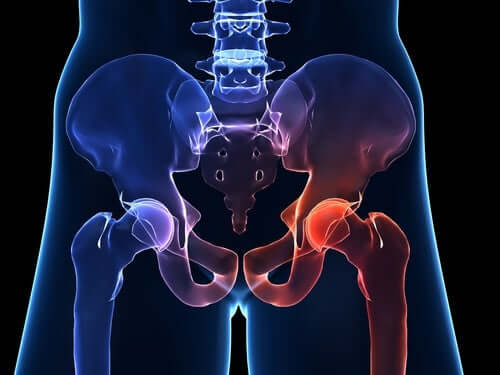

고관절은 흔히 엉덩이 관절이라고 불리며, 골반 쪽에 위치한 공-소켓(ball-and-socket) 형태의 관절입니다. 둥근 모양의 대퇴골두가 오목한 비구(acetabulum)에 맞물려 있어 골반과 허벅지를 연결하는 역할을 합니다.

이 관절은 체중을 지탱하고 보행, 달리기 같은 다리의 움직임을 가능하게 하는 핵심 구조입니다.